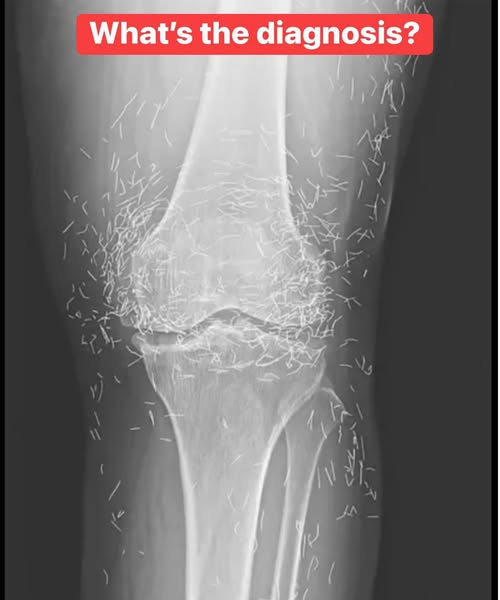

X-Ray Reveals Hundreds of Gold Needles in Woman’s Knees

South Korean Woman Found With Hundreds of Gold Needles Embedded in Her Knees A 65-year-old woman from South Korea discovered an unusual source of her persistent knee pain: hundreds of…